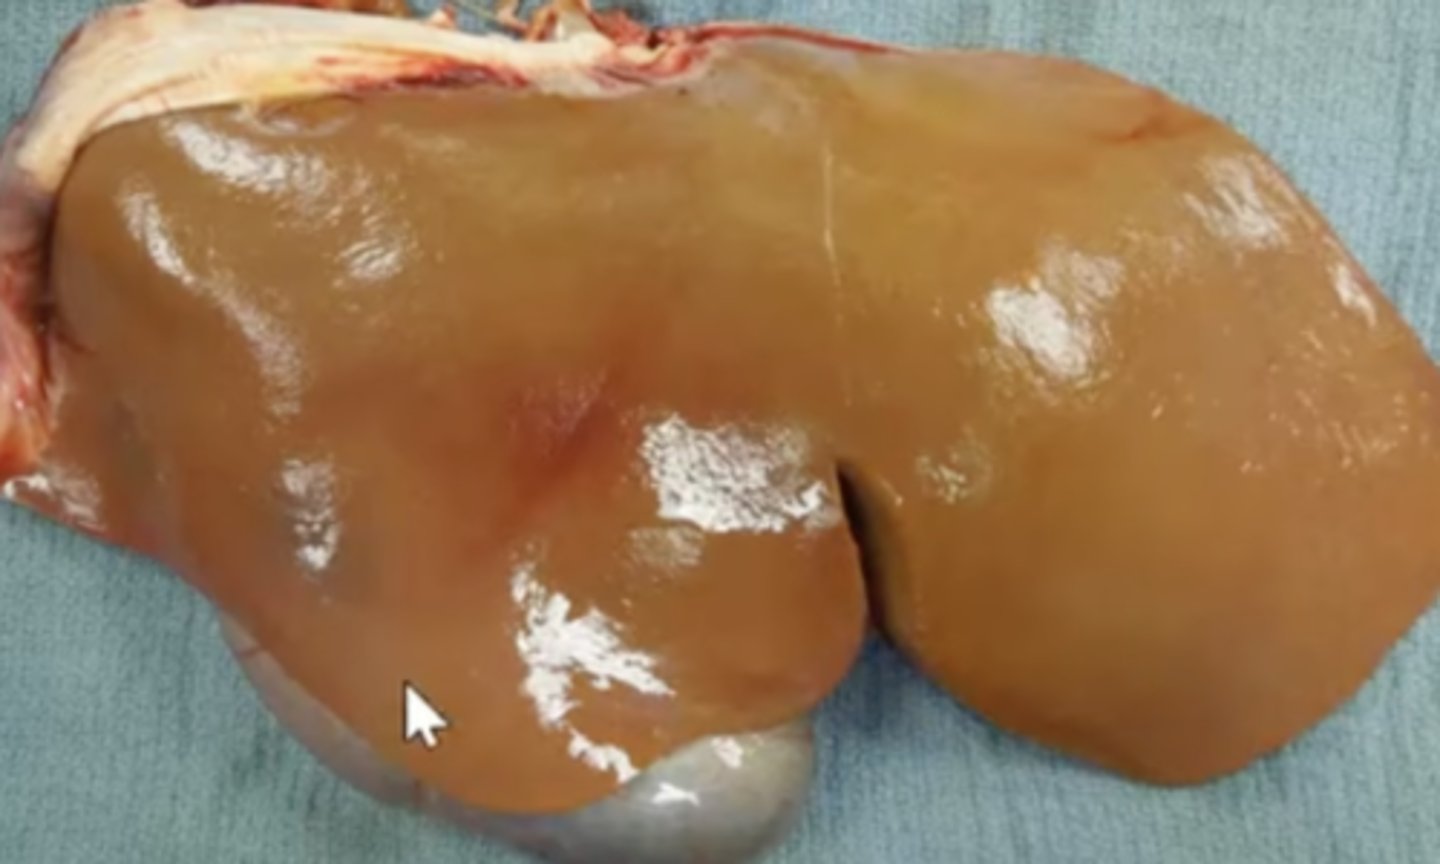

Amyloidosis

-result of abnormal folding of pathologic proteins

-deposited extracellularly

-waxy + hard liver

What has caused this gross appearance of this liver?

amyloidosis

-liver is enlarged, friable, and pale - can easily rupture

What has caused this gross appearance of this liver?

Amyloidosis

-red lines are from rib impressions

-caused by inflammation

What has caused this gross appearance of this liver?